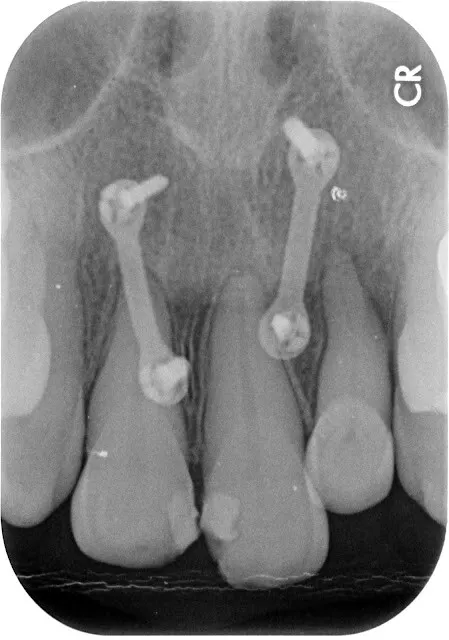

假牙材質4臨床案例---上門牙車禍+雕蠟模型